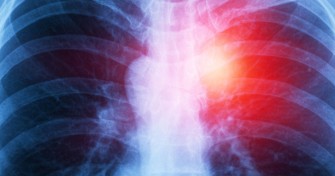

L’anaphylaxie est la manifestation la plus sévère de l’allergie : elle correspond à une réaction généralisée, à risque de récidive. Près de 5% des allergiques sont concernés par ce type de réaction. L...